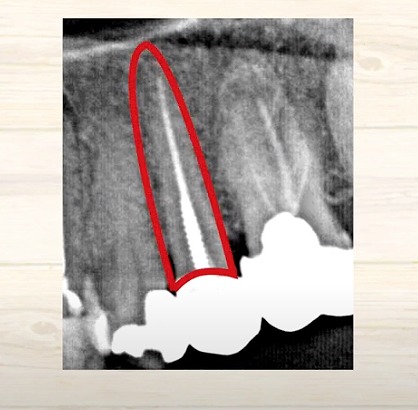

ですから、

硬い歯の頭があって

歯の根っこがあって、

ここの歯だと黒く写ってますね

そこは柔らかい

だから、歯の神経が生きているのではないかと考えます。

その神経血管が元々あったところに

人工のお薬、そして芯棒、そして被せ

このように一直線上に入るわけです。

そして

根っこと

被せモノが

段差なく移行的に入るように被せ物をされます。

これをレントゲンで撮影すると、ある患者さんの写真ですが、

歯の根っこ

薬を詰めている部分

芯棒

被せモノ

歯の根っこの周囲は

白い骨で覆われている

という風にイメージしていただくと

わかりやすいかもしれません